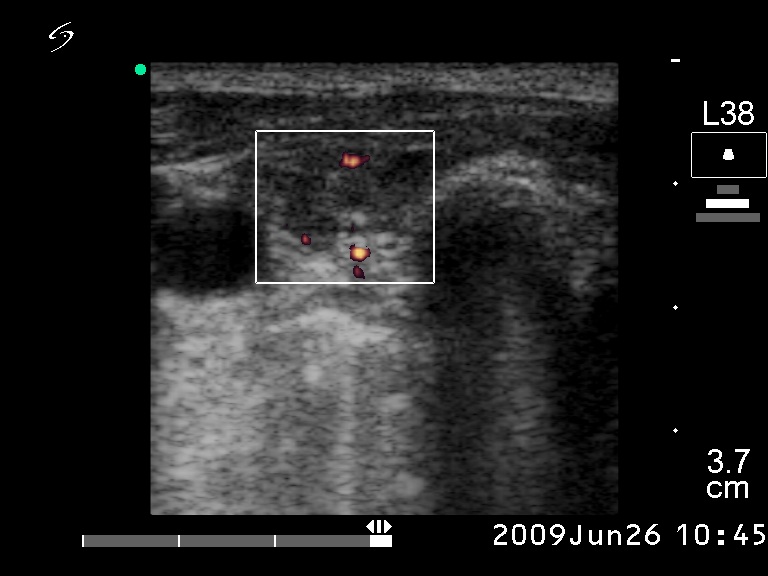

Ultrasonography. The right lobe was hypoechogenic and was not enlarged. The pattern in this lobe corresponded to Hashimoto's thyroiditis. There was a huge tumor in the left thyroid. The pattern of the left lobe varied from moderate to severe hypoechogenicity. The tumor was avascular.